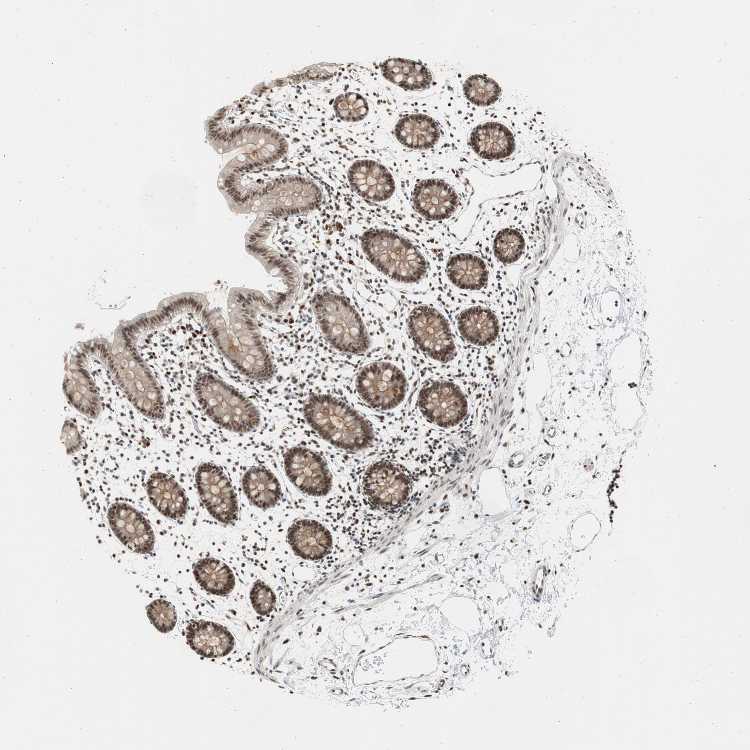

COLON - Antibody stainingi

Antibody staining in the annotated cell types in the current human tissue is reported as not detected, low, medium, or high, based on conventional immunohistochemistry profiling in selected tissues. This score is based on the combination of the staining intensity and fraction of stained cells.

Each image is clickable and will lead to virtual microscopy that enables deeper exploration of all samples and also displays staining intensity scores, fraction scores and subcellular localization as well as patient and tissue information for each sample.

Antibody HPA006914Antibody CAB004563

Endothelial cells MediumNot detected

Glandular cells MediumLow

Peripheral nerve/ganglion MediumNot detected